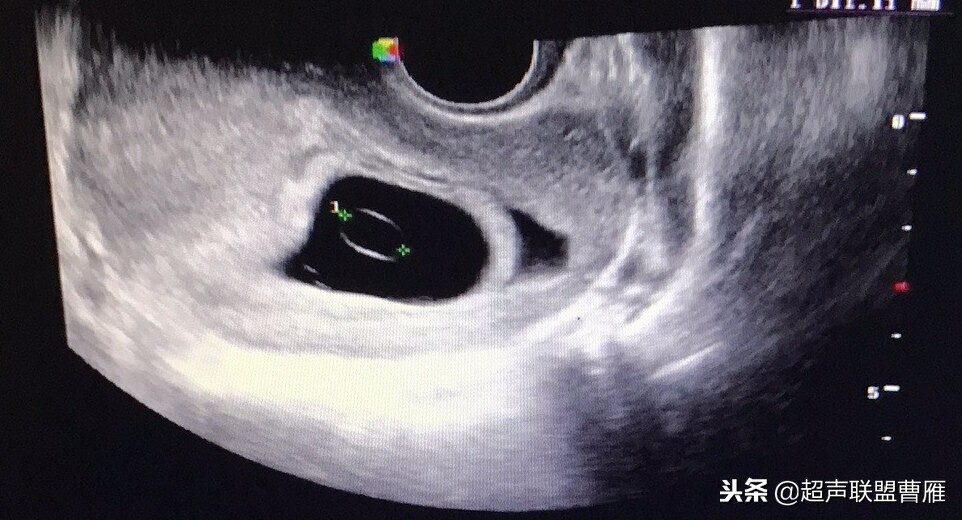

正常早孕卵黄囊声像图

早孕 胚芽 卵黄囊

5周+ 、6周+ 声像图

孕7周左右(胚芽11mm 卵黄囊)

胎芽 卵黄囊 心管搏动信号

宫内早孕 (7周左右)